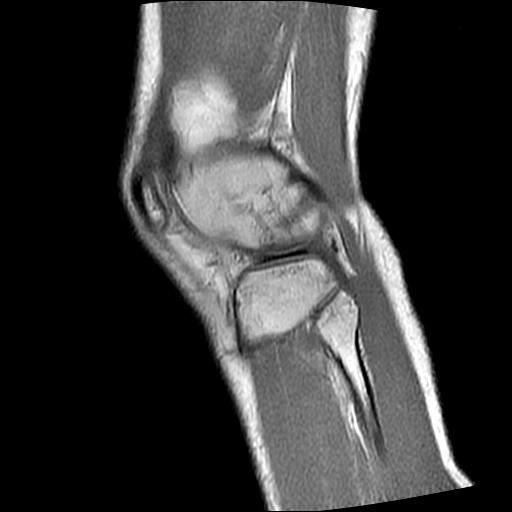

40岁男性,右膝关节外伤,x光平片示,髁间隆突撕脱骨折。

1、前交叉韧带撕裂;

前交叉韧带撕裂,关节腔积液.

半月板1-2级损伤   前交叉韧带撕裂伤   关节腔少量积液  诸骨未见新鲜外伤性改变

髁间隆突撕脱骨折;内侧副韧带损伤。

1、内侧副韧带撕裂;

2、前交叉韧带撕裂;

3、滑膜炎伴关节腔积液。

内侧副韧带撕裂及关节腔积液是肯定的,但是前交叉撕裂确定吗?会不会有容积效应的因素,因为前一张前交叉显示清楚,连续性良好,且较光滑。请问楼主有关节镜支持吗?我们医院也经常有这样的患者,但苦于没有关节镜,而无法对照、证实(除非完全断裂),出现了不同的诊断结果只能毫无意义的争论。

1、前交叉韧、内侧副韧带撕裂;

2、外侧半月板后角撕裂;

3、关节腔积液。4、髁间脊撕脱骨折。

除了关节积液外并无韧带撕裂,acl胫侧附着点有2束,正常情况下脂肪信号。此病例应加做压脂像以便观察是否有骨损伤。